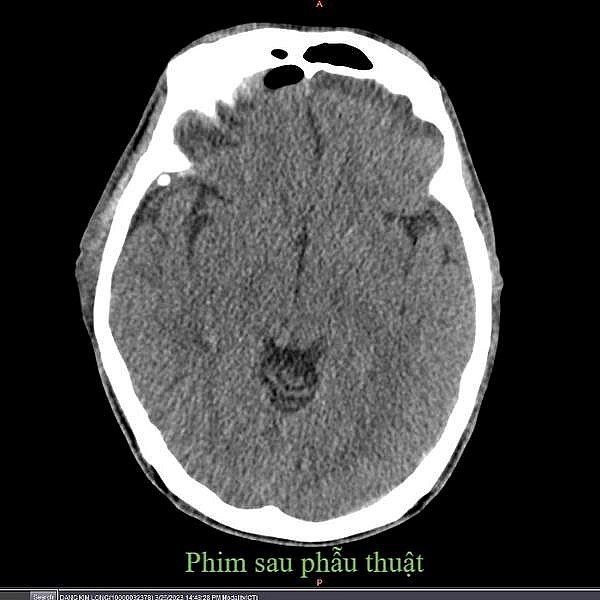

Hình ảnh cộng hưởng từ sọ não sau phẫu thuật. |

Tuy nhiên, sau hơn 1 tháng, người bệnh bắt đầu xuất hiện đau đầu, buồn nôn, người uể oải, mệt mỏi, dần dần đi lại không vững nên đã đến Trung tâm Y tế huyện Cẩm Khê kiểm tra. Tại đây, các bác sĩ đã tiến hành thăm khám, chụp cộng hưởng từ sọ não và sĩ yêu cầu mổ cấp cứu do tụ máu dưới màng cứng.

Bác sĩ chuyên khoa II Giang Hoài Đức, Trưởng khoa Ngoại Tổng hợp, cho biết: Các bác sĩ phải khoan sọ một lỗ, bơm rửa dẫn lưu máu tụ để lấy máu tụ dưới màng cứng. Đây là phương pháp tối ưu, không can thiệp mổ hộp sọ, giảm nguy cơ biến chứng hậu phẫu, phục hồi nhanh.